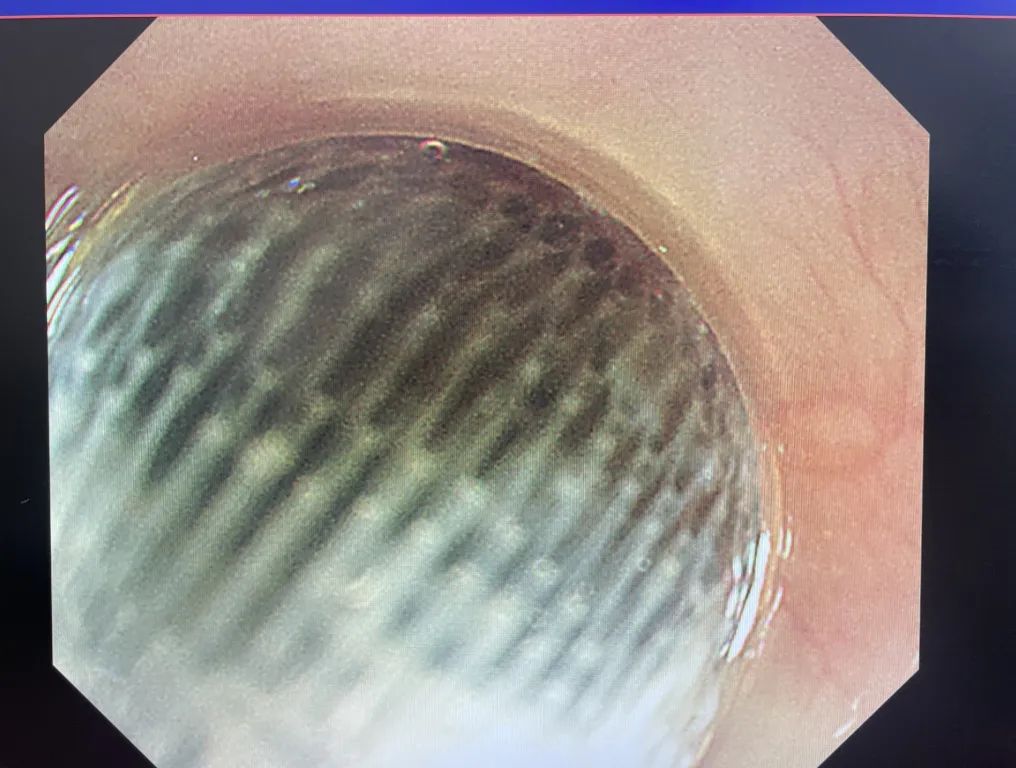

在胃镜的引导下,刘伟锋很快找到了异物。在发现异物表面光滑后,他特地选用了网兜型异物钳开展取出工作......20分钟后,异物被成功“网”出。经查,小明的食管无出血、穿孔等情况。

被网兜型异物钳“网”住的异物

看看这个被取出的玩具,你家是不是也有?